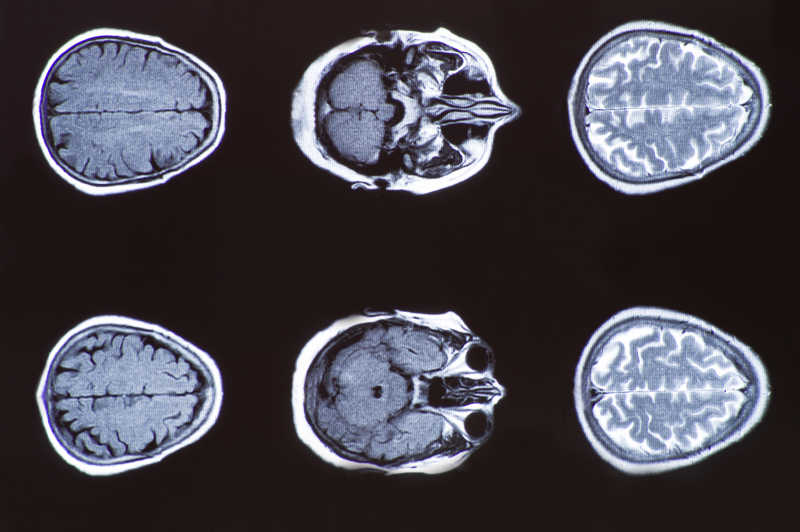

- 核磁共振

- 扫描

- 脑